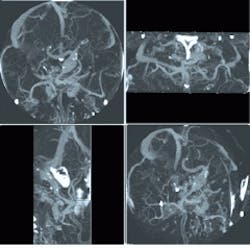

Four views at different angles from the same CT data set show bulbous vascular defects in the Circle of Willis at the base of the brain. These images were created using a VIS-optimized library, media Lib, for CPU-based image processing. Each square represents 5 5-in. slide of tissue.

Medical imaging is rich in fixed-point processing and is an ideal application for the VIS instruction set, which can accelerate nearly any fixed-point signal processing (see figure). The parallel math can be applied in a number of places in acquisition-end signal processing. Operations such as one- and two-dimensional convolution, fast Fourier transforms, frequency-domain filtering, and nonlinear filtering can all be accelerated, sometimes by as much as a factor of seven.

Image reconstruction, particularly the back projection used in computed tomography (CT), also benefits from the parallel-processing capabilities of these extensions. The VIS instruction set is also applicable in the visualization of the image data from any medical modality. For example, in x-ray imaging, it can be used for digital subtraction angiography. The set can be used for fast pan and zoom, which is particularly useful for digital mammography, or image compression, which is important for ultrasound.

Even with this breadth of capabilities, the most impressive use of the VIS instruction set is probably for volumetric rendering of data from

3-D modalities such as CT

and MRI. Here, the Sun

3-D addressing instruction (ARRAY) comes into play. This instruction was developed because cache efficiency and memory bandwidth are often the limiting factors in the performance of volumetric rendering on a general-purpose CPU.